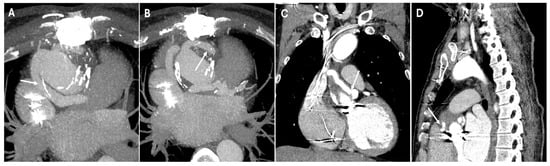

| Pseudoaneurysm | Suture failure, infection, chronic mechanical stress | Contrast-filled sac adjacent to graft, narrow neck | High rupture risk |

| Endoleaks (TEVAR) | Incomplete sealing, graft migration | Persistent contrast enhancement outside stent graft lumen | Can lead to aneurysm expansion and rupture |

| Graft Migration (TEVAR) | Insufficient landing zone, poor fixation | Displacement > 10 mm on sequential imaging | May cause endoleaks or malperfusion |